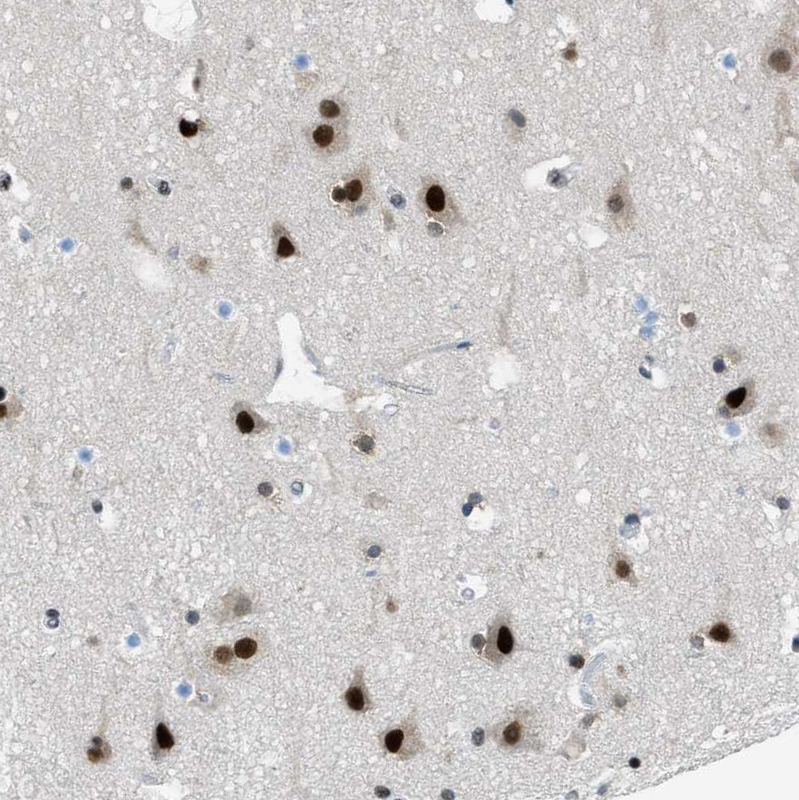

Immunohistochemistry analysis in human cerebral cortex and liver tissues using HPA017015 antibody. Corresponding GATAD2B RNA-seq data are presented for the same tissues.